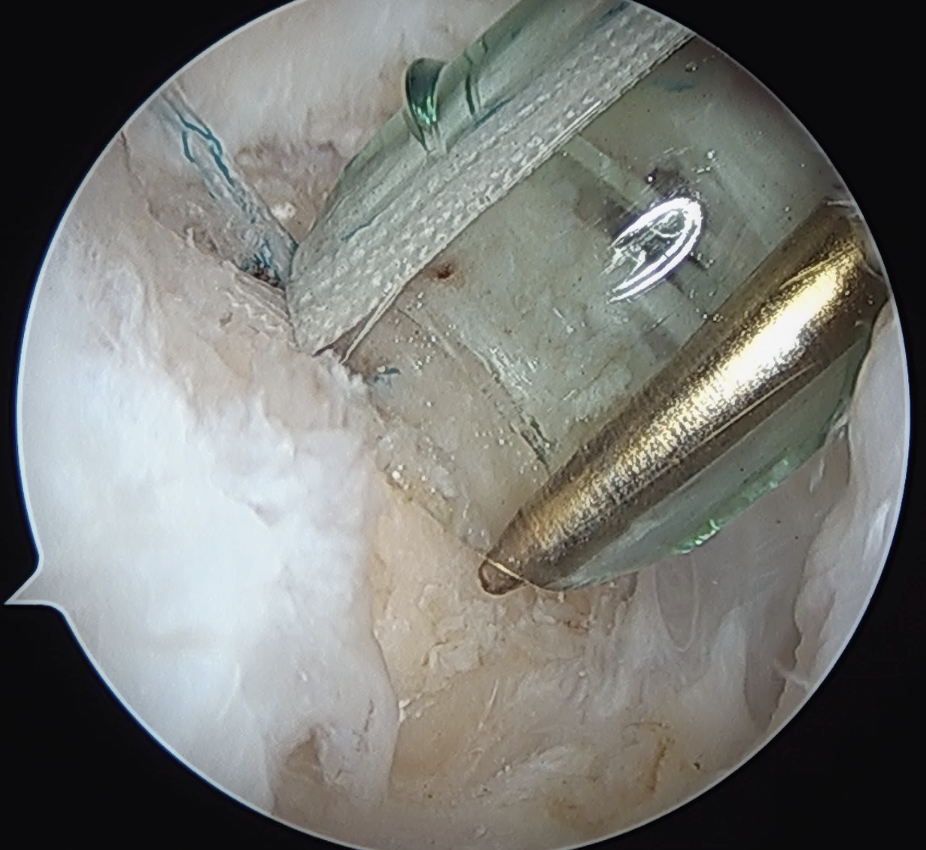

Trans-osseous equivalent / suture bridge

- cross sutures from medial row to lateral row

- increase contact between cuff and footprint

Double row / suture bridge

- use medial row sutures

- secure in knotless lateral row anchors